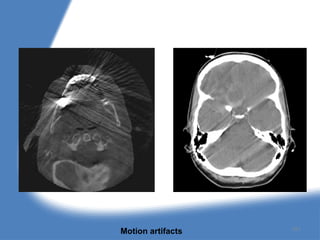

1. Motion artifacts :

During scanning if the patient moves it will produce

vertical or diagonal bands of artifacts. Motion

artifacts occurs because the back projection

algorithm assumes stationary object geometry. If

motion occurs halfway through the CT scan

acquisition, the first half of the projection data will

back project the anatomy in a different orientation.

The image will appeared blurred in the area where

the motion occurred and give rise to image

ghosting ; i.e. the appearance of two superimposed

image.

Motion artifacts 151